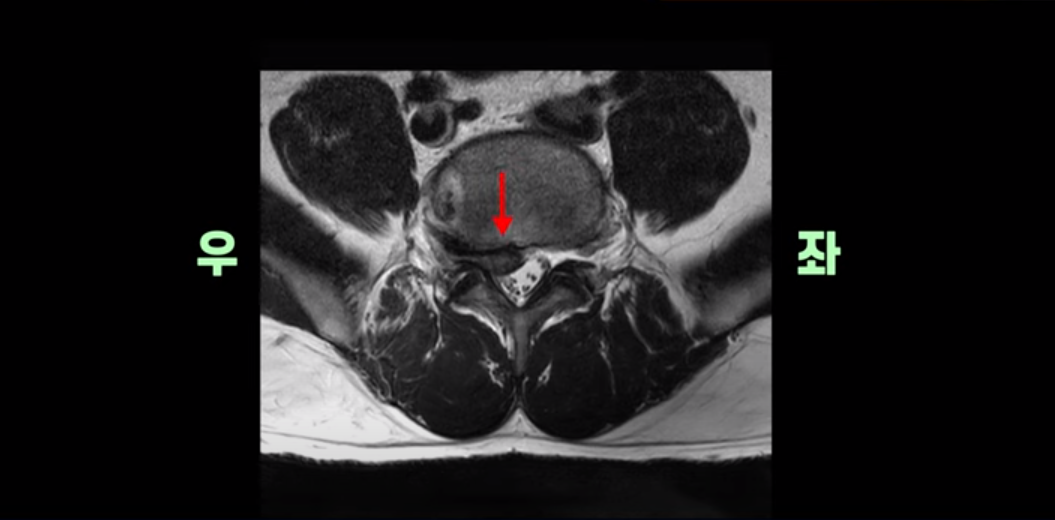

MRI를 보면 이분 5번 1번 디스크가 심하게 터져서 밀려 올라가 있습니다.

횡단면을 보면 우리 병원 치료 후기에 있는 다른 디스크 파열 환자분들에 비해서는 파열이 덜 심해 보일 수도 있지만,

이분은 파열이 오른쪽으로 치우쳐 신경이 빠져나가는 추간공을 완전히 막고 있습니다.

다른 신경 구멍들은 열려있는데 비해 5번 1번 구멍은 까맣게 막혀있습니다.

이렇게 심하게 신경가지가 눌리니까 극심한 통증은 당연하고 발목에 마비가 생겨 힘이 빠지는 족하수 증상까지 생겼습니다.